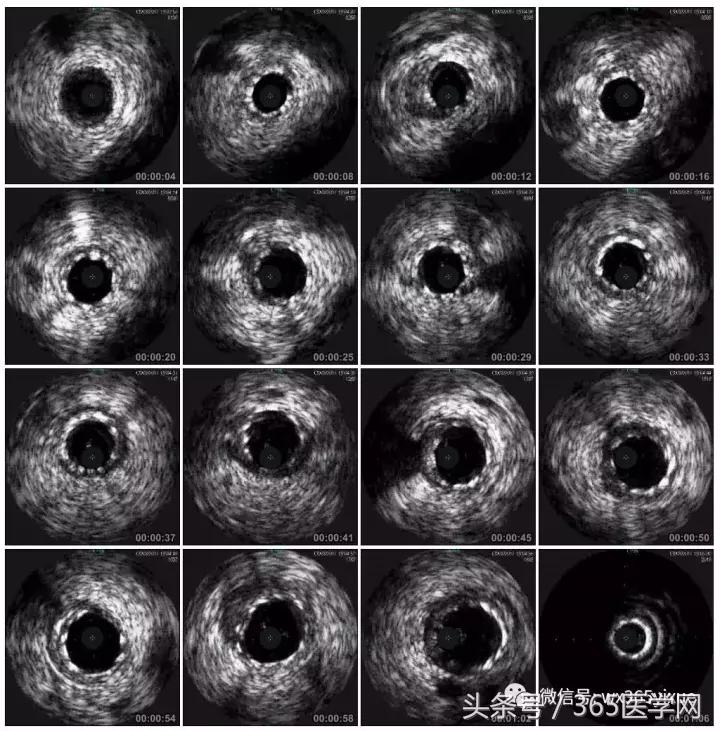

RCA闭塞段球囊扩张后IVUS

支架术后IVUS